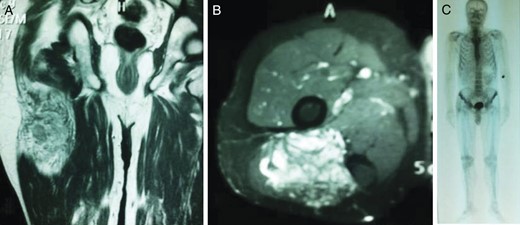

A 74-year-old man presented to the orthopedics outpatient clinic with painless swelling on his right leg that had developed progressively in the last 3 months. He underwent right radical nephrectomy for RCC 7 months prior. A pathological examination of the right kidney demonstrated the presence of clear cell carcinoma and Fuhrman grade IV (pT2 N0 Mx). On physical examination, an 8 × 6 cm hard mass was palpable on the lateral aspect of his right leg. MRI of his right leg revealed a 10 × 8.5 × 5.5 cm tumor located in the gluteus medius muscle (Fig. 3A and B). Computed tomography, ultrasonography and MRI did not reveal any liver or retroperitoneal lymph node metastasis. A total body bone scan of the patient showed no abnormalities (Fig. 3C). Biopsy of the muscle mass documented an RCC metastasis (Fig. 4A and B). The mass was completely removed from the right leg. The patient underwent three cycles of immunotherapy regimen, including IFN-α.

Coronal (A) and axial (B) T2-weighted axial magnetic resonance image of the right gluteus medius muscle showing avid enhancement of the soft tissue component. (C) Total body bone scan image.